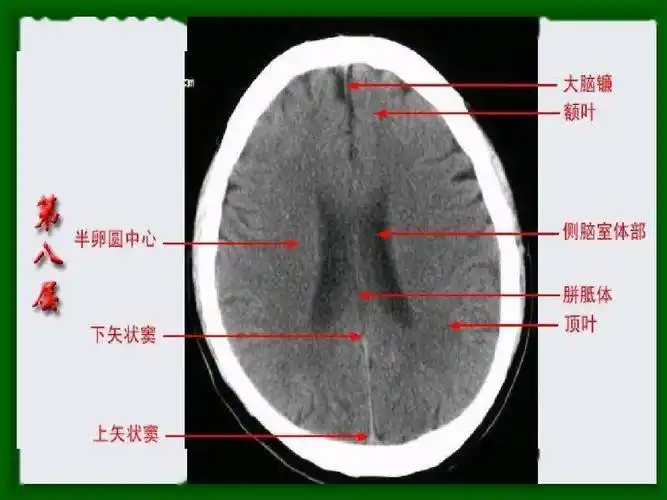

头部ct影像解剖

头颅ct断层解剖

详细标注版——颅脑ct正常解剖图谱_中央_小脑_纤维

珍藏| 颅脑ct断面解剖彩色图谱